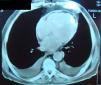

Complementary diagnostic exams included the latest echocardiographic modalities, notably assessment of LV strain and longitudinal early diastolic mitral annular velocity (E’). LV longitudinal strain was preserved, as was early diastolic mitral annular velocity (septal E’: 8.4cm/s; E/E’: 8.3) (Figure 1), with a respiratory variation of >25%. However, circumferential strain was reduced, a finding that supported a diagnosis of CP. As in the exam performed 11 years previously, chest CT showed diffuse pericardial thickening, but this time focal pericardial calcification was also observed. There were no significant parenchymal lung lesions (Figure 2). Cardiac magnetic resonance imaging (MRI) confirmed mild pericardial thickening in the basal and mid ventricular walls, reaching 3mm in the lateral LV wall (normal <2mm). Ventricular volumes and right ventricular EF were normal (LVEF 40%, moderately impaired), and there was mild mitral regurgitation. No delayed enhancement study was performed, as the patient did not wish to continue the exam.

Chest CT and cardiac MRI will detect a thickened pericardium in CP, but the information they provide is merely anatomical and does not necessarily reflect pathophysiological changes.5 In the case presented, these two exams supported our principal diagnostic hypothesis by documenting pericardial thickening with focal calcification. However, it should be remembered that 18% of patients with surgically proven CP present normal pericardial thickness and so the absence of thickening does not exclude CP.6